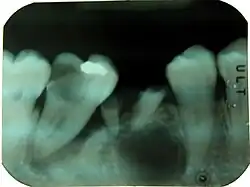

Periapical readiograph of lower right teeth, showing a large carious lesion in the distal of the lower right second molar. The same tooth also has an extensive periodontal defect. At this stage, without further information, it is difficult to tell which process has occurred first and lead to the death of the pulp.